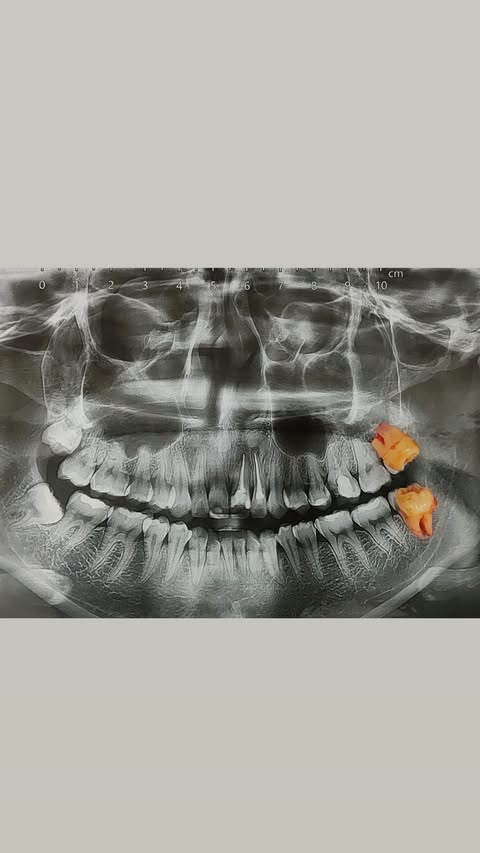

До и после лечения

Результат имплантации

До и после